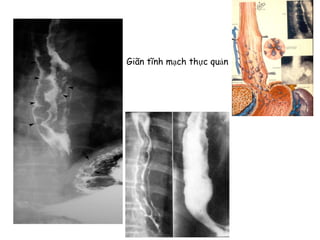

Giãn tĩnh mạch thực quản

Giãn tĩnh mạchthực quản